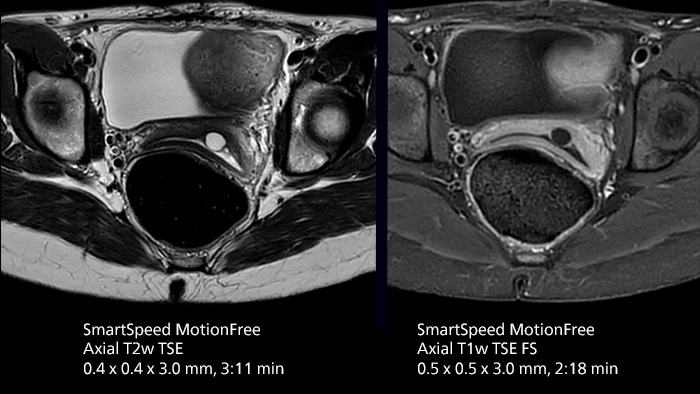

After using Philips SENSE, Mermaid Beach had adopted Compressed SENSE that offers a k-space sampling approach to speed scans while preserving details. “And now SmartSpeed enables denoising the sparse under-sampling in a new way that has allowed us to increase acceleration and bring image quality to a whole new level,” notes Kennedy, “It’s truly revolutionized our MRI work space, especially for difficult patients.”

Philips SmartSpeed has multiple approaches to denoising. Raw k-space data, coil sensitivity and coarse background information are all used and reconstructed with artificial intelligence (AI) to provide true resolution in shorter scan times1 with more sequences. Kennedy states, “I noticed that since the introduction of SmartSpeed, our day is a lot less stressed. When complicated exams need extra time, we just get on with them. And if we need to do something new or extra, we have the time for it and our workflow is still a lot more efficient.”

In addition to workflow benefits, Kennedy highlights the improvement in their diagnostic confidence. “The quality of output is so much higher than what we believed was possible, and it is very consistent across multiple patients. SmartSpeed made it feasible for us to include extra sequences in our exams and still maintain routine scanning times. This allows us to make a surprising number of diagnoses that we couldn’t have appreciated before with our previous protocol. We’ve gotten an extremely positive response from our referrers.”

The broad applicability of SmartSpeed allowed the imaging center to use this technology across many scan types, including non-cartesian imaging as used for motion correction in uncooperative patients or challenging anatomies.

“We use SmartSpeed frequently on difficult areas such as the abdomen and chest where it is common to see respiratory motion and other bowel motion,” says Kennedy. In MSK scans they use SmartSpeed not only for speeding up their exams, but also to reduce slice thickness and improve resolution “We may be increasing the number of slices, but we’re still doing this in less time than we were previously.”